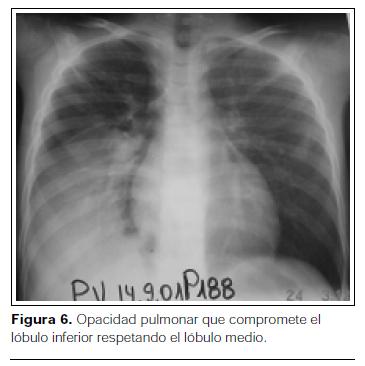

- Distribución no segmentaria: la infección en la neumonía bacteriana, por su forma de propagación, no respeta los límites entre los segmentos (distribución no segmentaria)(figuras 4, 5 y 6) (1,8).

- Progresión: la consolidación de la neumonía comienza generalmente en el parénquima subpleural. Típicamente se observa una opacidad pulmonar que progresa en dirección centrífuga desde un centro subpleural y puede afectar uno o varios segmentos de un mismo lóbulo o de lóbulos pulmonares diferentes, pudiendo comprometer los segmentos pulmonares de manera parcial o completa; lo más frecuente es que la enfermedad se limite a un solo lóbulo, pero en ocasiones la infección tiene lugar simultáneamente en dos o más (figuras 5, 6 y 7).